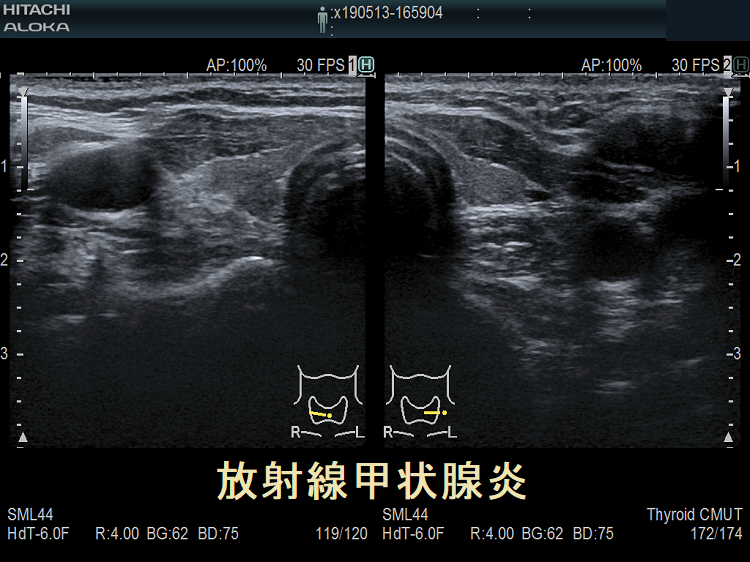

子宮頸がん頸部リンパ節転移に放射線外照射した後の放射線甲状腺炎 超音波(エコー)画像 超音波(エコー)画像 (拡大);内部は等エコー、比較的均一。